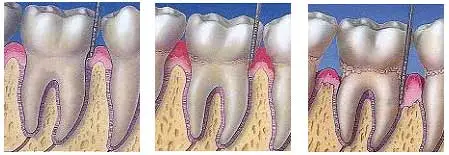

Believe it or not, gum problems are the most common diseases affecting the human population.Most of the people think that teeth are the only element of a beautiful smile. However, the fact is that the size, shape, integrity and health of gum tissue greatly influence the aesthetic appearance of even the most perfect teeth. Too much gum tissue can lead to teeth that look short and wide while too little gum tissue can lead to exposure of root surfaces of teeth that look way too long. Periodontics is an area of expertise that deals with gum treatments and bone supporting the teeth. In health, the gums firmly grip the neck of the tooth. If food is allowed to accumulate between the tooth and the gum margin, it forms plaque along with the microbes. The resultant irritation of the gum margins produces a condition called as GINGIVITIS characterized by redness, bleeding and swelling of the gums. If proper attention is paid at this stage the condition is perfectly reversible. However in untreated cases the condition further deteriorates leading to the destruction of the tooth-supporting tissues. The condition is then called PERIODONTITIS or PYORRHOEA. At this stage the teeth start shaking, they are unable to withstand chewing forces, pus forms in the gums and foul smell starts from the mouth.

1. Non-surgical treatment involves scaling and polishing of teeth. The procedure aims to remove food particles, plaque and calculus accumulating around the tooth. The effectiveness of the procedure depends largely on the stage of the disease, the efficiency of instrumentation and the maintenance on the part of the patient. No matter how good we are at brushing, we cannot achieve 100% efficiency in cleaning. So, small depositions continue to occur on a daily basis. For long term maintenance of teeth, it is therefore advisable to go in for a professional cleaning once in six months even if you do not have an evident gum problem. 2. The Surgical approach to treatment is usually recommended for resistant cases where complete removal of the irritants from root surface of the tooth is not possible by scaling alone due to the deep penetration of the deposits. The procedure also called as flap surgery or flap operation involves reflection of the gums by 1-1 1/2 mm and debriding the area under local anesthesia with direct visualization of the deposits. The procedure is completely painless and involves minimum post-operative pain or discomfort. In certain cases however it is possible to re grow the lost bone by use of certain bone substitutes called Bone grafts. Such cases provide the ideal outcome of therapy by regenerating the lost tissues.